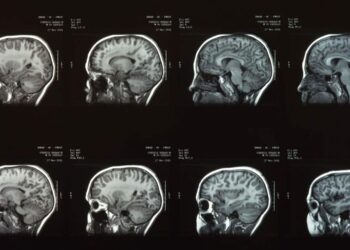

Cientistas encontraram um “interruptor” no cérebro que pode desligar a dor

Pesquisadores da Universidade Duke, nos Estados Unidos, identificaram uma área no cérebro de ratos capaz de modificar a sensação de ...